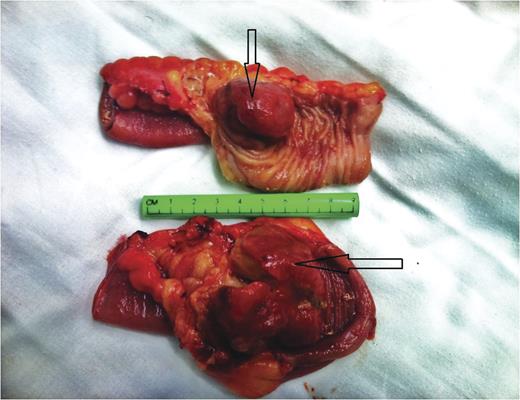

Under general anesthesia, patient in supine position, a midline laparotomy was performed. A large amount of abdominal fluid was aspirated and sent for culture and cytology. During running of the bowel at the level of 20 cm from the ligament of Treitz, an intussusception with a palpable intraluminal mass was found. Another intussusception 120 cm distal to the first was also noted (Fig. 2). No other pathologies were found. Double enterectomies with end-to-end anastamoses were performed. The patient was discharged home on Day 5 post op. Pathological analysis revealed polypoid and infiltrating intraluminal lymphoid proliferation (Fig. 3), extending to serosa and exhibiting diffuse aspect composed of medium-sized B-cells: pattern of Burkitt's Lymphoma. Abdominal fluid cytology analysis showed the presence of atypical lymphoid cells.

The surgical specimen comprised two segments of resected small bowel. Note the intraluminal mass (lead point) that caused the intussusception (arrows).